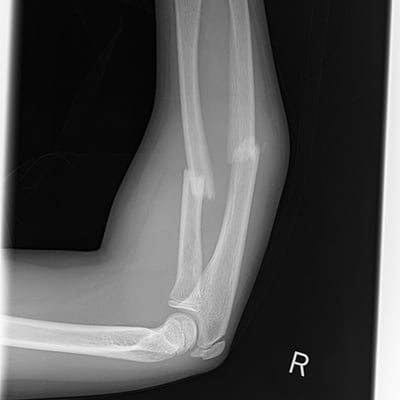

This module will help you achieve optimal images when performing elbow, humerus, shoulder, and scapula examinations. Patient preparation and positioning are discussed, as well as technical settings and patient instructions. Descriptions and images of the expected anatomical structures are included, as well as image evaluation criteria.

This module will help you achieve optimal images when performing trauma examinations of the shoulder, upper extremities, lower extremities, and cross-table lateral spine. Patient preparation and positioning are discussed, as well as technical settings and patient instructions. Descriptions and images of the expected anatomical structures are included, as well as image evaluation criteria.